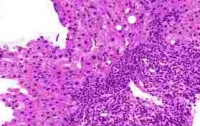

57% случаев цирроза печени и 78% случаев первичного рака печени вызывают вирусы гепатита В и С